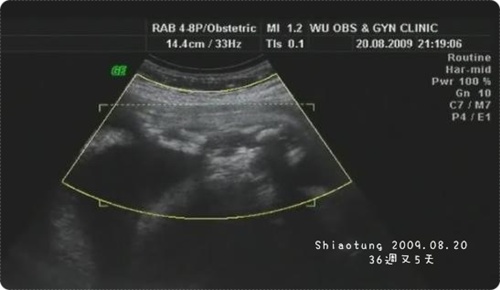

懷孕週數:36+5

胎兒體重:約29xx~30xxg

看看寶寶大小→每星期約多兩百公克左右

看看羊水量→正常

胎盤位置→正常

臍帶位置→正常